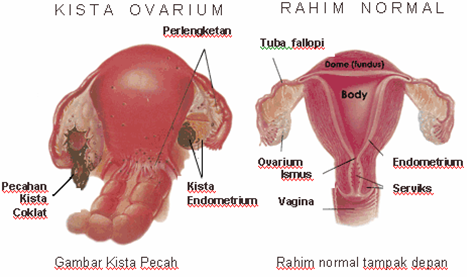

Kista ovarium adalah kantung kecil berisi cairan yang berkembang dalam ovarium (indung telur) wanita. Kebanyakan kista tidak berbahaya. Namun, beberapa dapat menimbulkan masalah, mulai dari nyeri haid, kista pecah, perdarahan, hingga penyakit serius, seperti: terlilitnya batang ovarium, gangguan kehamilan, infertilitas hingga kanker endometrium.

Perbedaan Kista dengan Mioma

Kista berbeda dengan mioma. Kista berbentuk cairan, sedangkan mioma berbentuk massa solid (tumor). Kista biasanya tumbuh dalam ovarium (indung telur) wanita, sedangan mioma pada dinding rahim wanita. Pada kenyataannya, seorang wanita bisa mengalami baik kista maupun mioma secara bersamaan.

Kista Endometrium:

Disebut juga endometriosis. Jenis ini terjadi ketika jaringan lapisan rahim (endometrial) hadir dalam ovarium wanita. Biasanya berisi darah kecoklatan, dan ukurannya berkisar antara 2 cm hingga 20 cm. Karakteristiknya: menyerang wanita usia reproduksi, menimbulkan sakit nyeri haid yang luar biasa, dan mengganggu kesuburan (fertilitas).